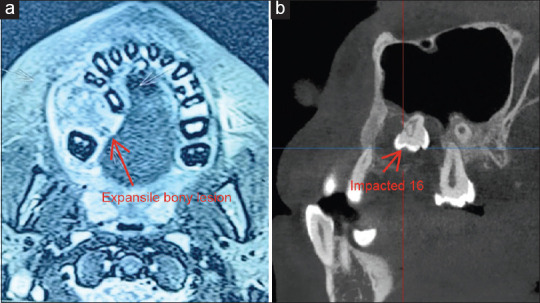

Patient concerns: A 14-year-old male patient reported with a chief complaint of swelling in the right upper back tooth region for four months.

Diagnosis: Incisional biopsy of the lesion shows numerous dilated and thin-walled blood vessels and focal areas of chronic inflammatory cell infiltrate beneath the epithelium suggestive of angiofibroma.

Treatment: Surgical excision of the lesion along with curettage was done under general anaesthesia. On histopathologic examination, the lesion revealed loose connective tissue stroma with mesenchymal cells and multinucleated giant cells suggestive of CGCG.